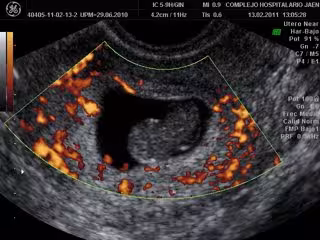

A todas ellas se les practicó una ecografía, se les extrajo una muestra sanguínea para realizar determinaciones analíticas y se les pasó un cuestionario. En total, se recogieron 131 variables en cada participante.